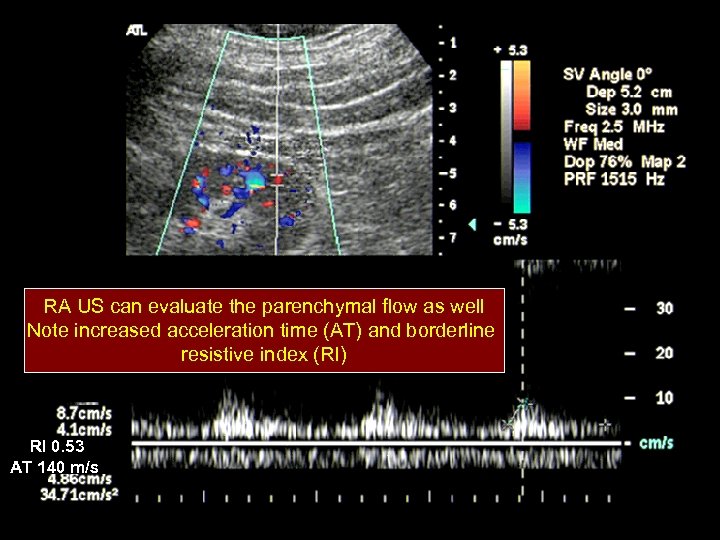

RA US can evaluate the parenchymal flow as well Note increased acceleration time (AT) and borderline resistive index (RI) RI 0. 53 AT 140 m/s